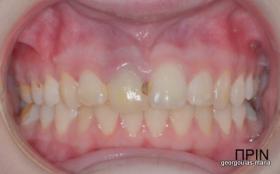

ΑΠΟΚΑΤΑΣΤΑΣΗ ΑΝΩ ΚΕΝΤΡΙΚΟΥ ΤΟΜΕΑ ΜΕ ΜΟΝΗΡΕΣ ΕΜΦΥΤΕΥΜΑ

Η κοπέλα αυτή ήρθε στο ιατρείο με κάταγμα στον δεξιό άνω κεντρικό τομέα. Το δόντι είχε απονευρωθεί στο παρελθόν και είχε αποκατασταθεί με βιδωτό άξονα κ ανασύσταση με ρητίνη και το αισθητικό αποτέλεσμα ήταν φτωχό. Η ασθενής ήθελε να είναι καλυμμένη αισθητικά για όσο χρονικό διάστημα θα διαρκούσε η θεραπεία. Πραγματοποιήθηκε τομογραφία κωνικής δέσμης (CBCT) στην περιοχή και αποφασίστηκε να γίνει εξαγωγή του δοντιού, διατήρηση του όγκου του φατνίου και 3 μήνες μετά τοποθέτηση εμφυτεύματος με ταυτόχρονη χρήση μοσχευμάτων σκληρών κ μαλακών ιστών  για βέλτιστο αισθητικό αποτέλεσμα. Το εμφύτευμα αποκαταστάθηκε με υβριδικό κολόβωμα από διπυριτικό λίθιο και ολοκεραμική στεφάνη από διπυριτικό λίθιο (Emax). Καθ’ όλη τη διάρκεια της θεραπείας, η ασθενής ήταν καλυμμένη αισθητικά με γέφυρα Meryland  συγκολλημένη στα δύο διπλανά δόντια. Μετά την οστεοενσώματωση του εμφυτεύματος και πριν την τελική αποκατάσταση, τοποθετήθηκε στο εμφύτευμα προσωρινή εργασία με σκοπό τη βελτίωση των ούλων.